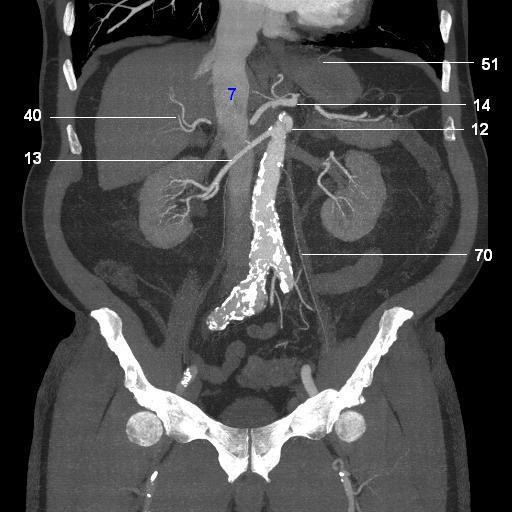

7.   IVC

12. SMA origin

13. right renal artery

14. celiac artery

40. right hepatic artery

51. left inferior phrenic artery

70. testicular artery